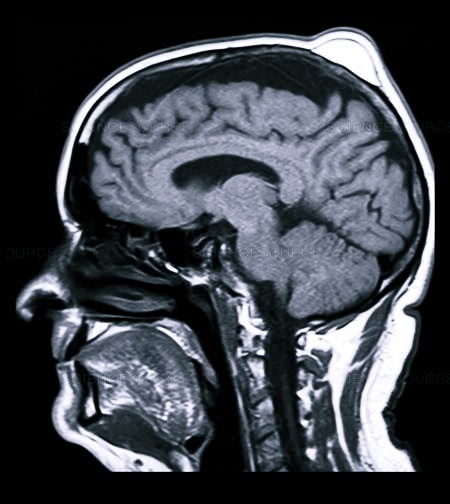

При проявлении вышеуказанных симптомов необходимо сразу обратиться к врачу, чтобы удостовериться в отсутствии тяжелого повреждения головного мозга или кровоизлияния. Для того чтобы определить, насколько серьезна травма, необходимо пройти МРТ или КТ.

При черепно-мозговой травме используют рентген, МРТ и КТ, нередко проводится ангиография (исследование сосудов мозга с введением контрастных препаратов).